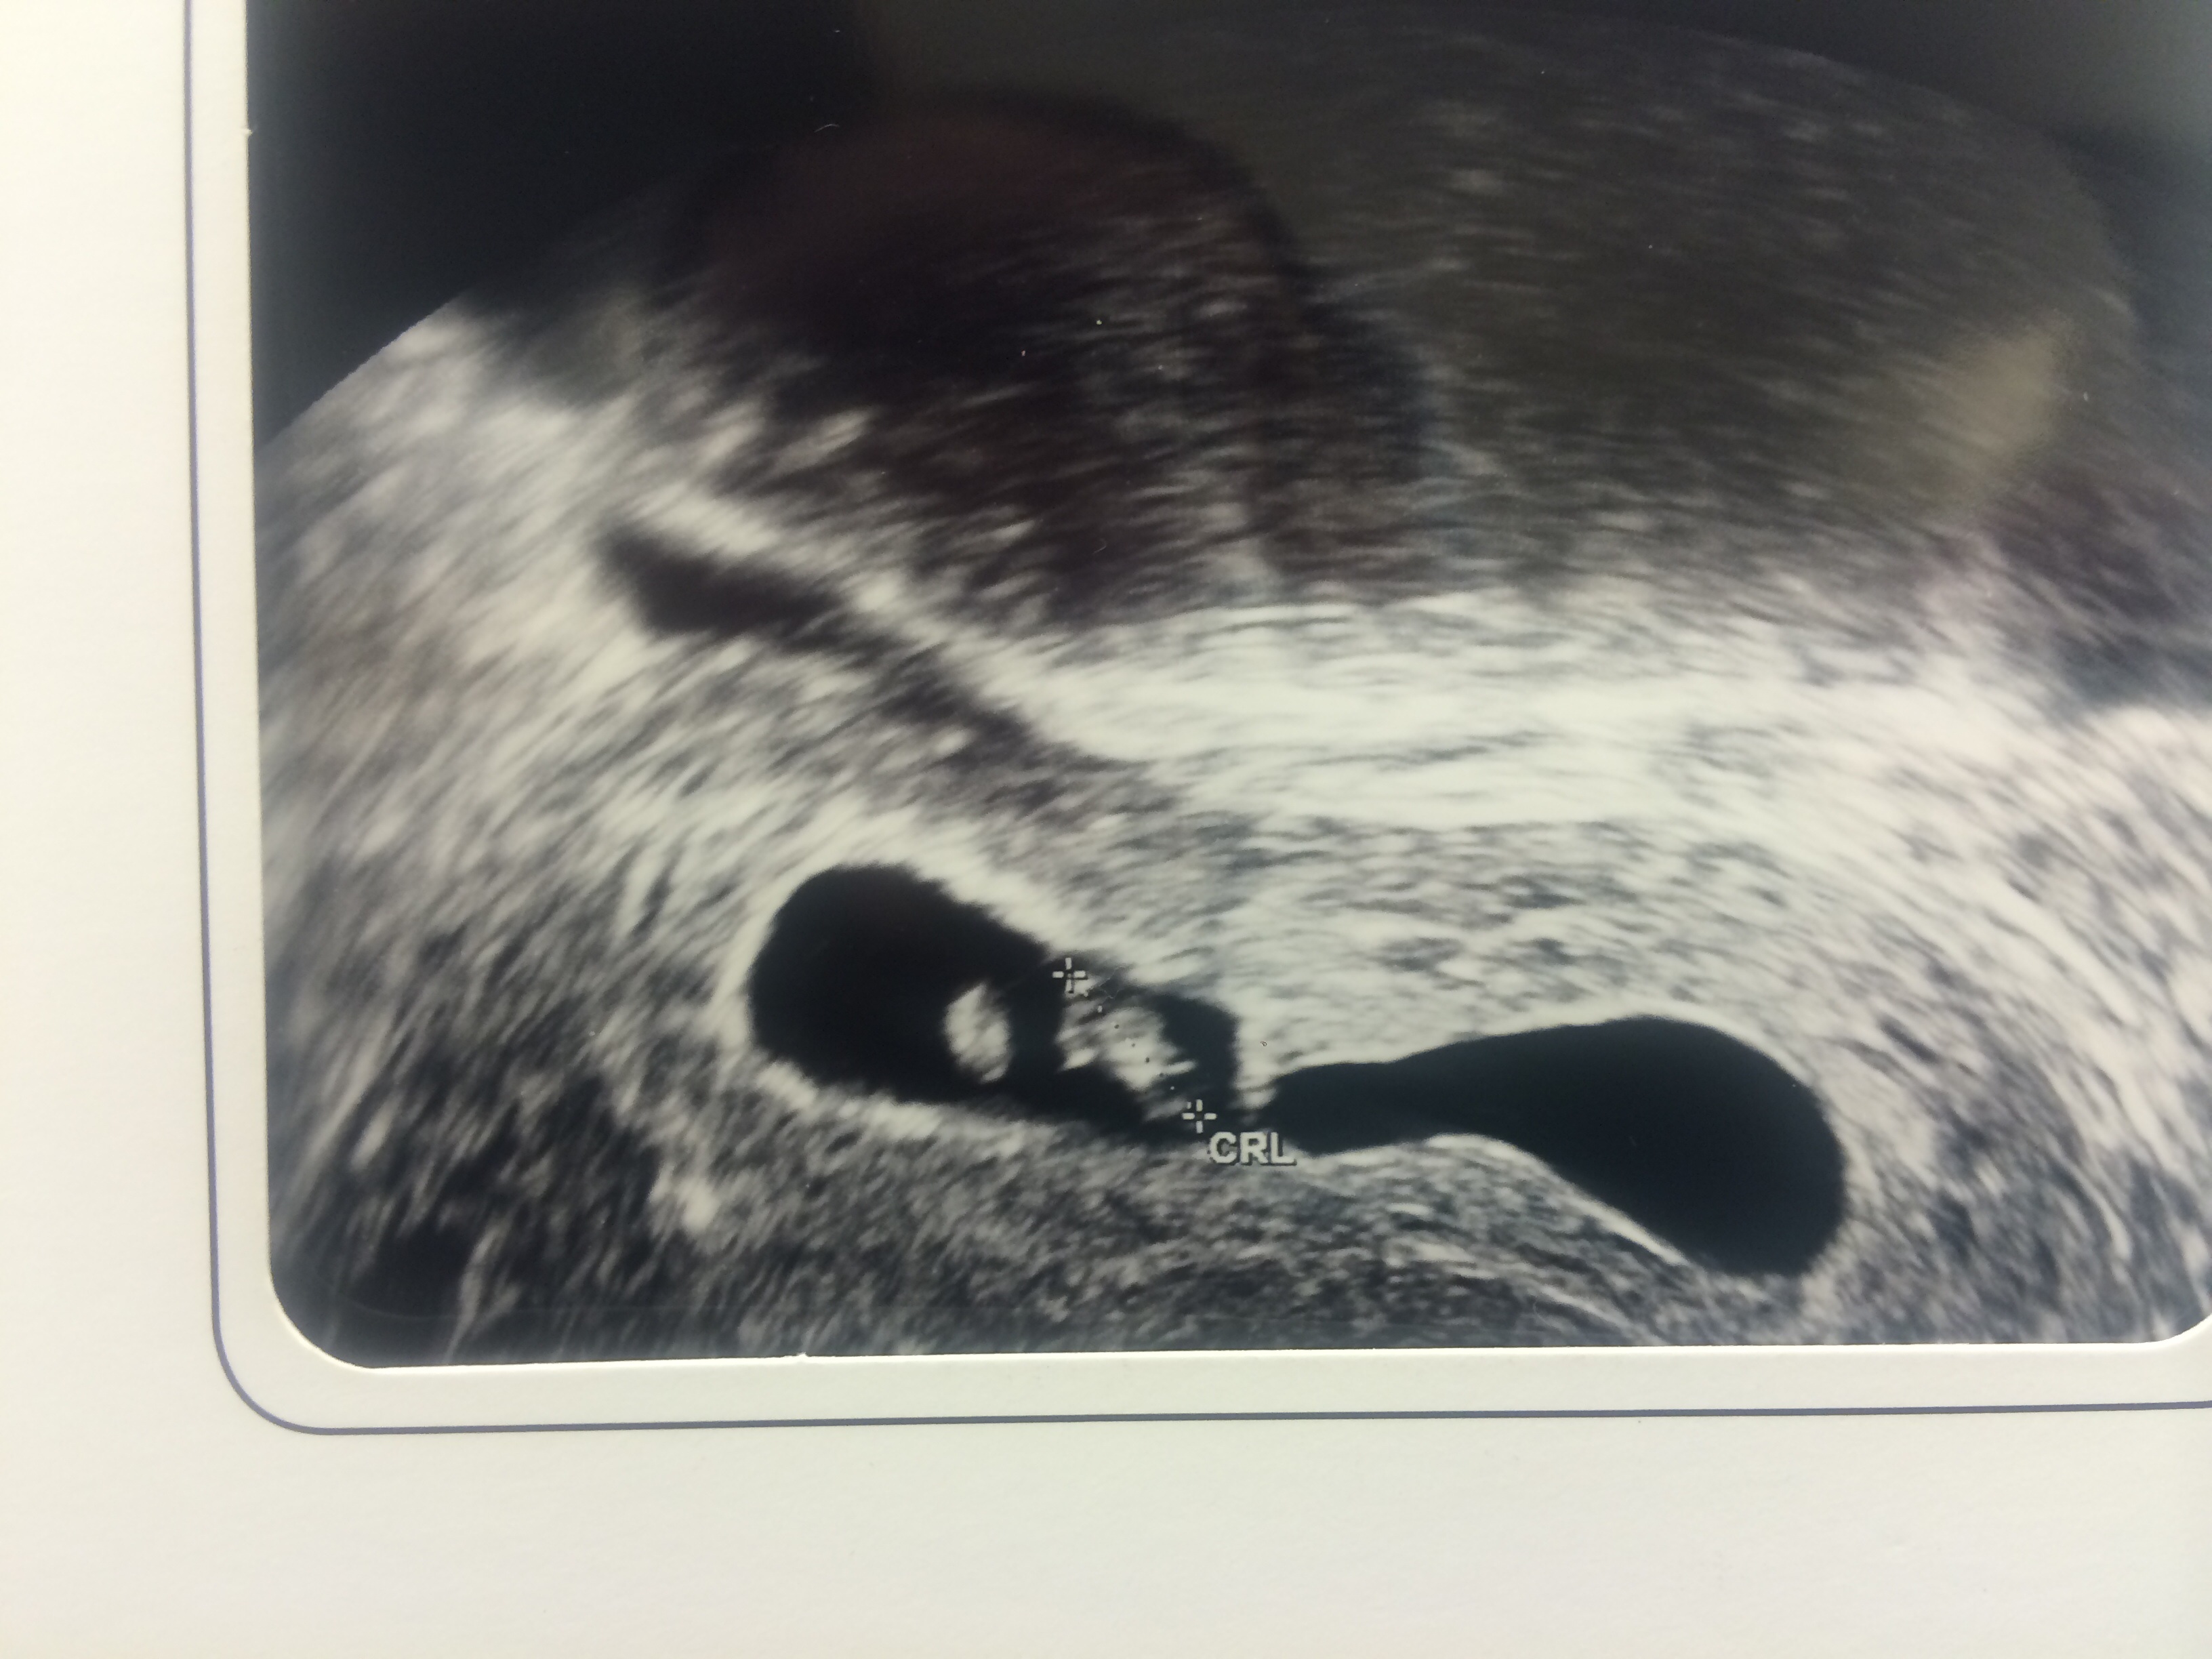

Had my follow up ultra sound to see if anything had progressed where the baby was measuring behind. We saw 2 sacs but only one baby so the ob thinks that's why I was bleeding a couple weeks ago. I feel bad that I'm not more broken up about it because I did loose a baby but I'm over the moon that there is still one in there and we saw the heartbeat! I'm now due 4-15-15 but really can't bring myself to leave this board.